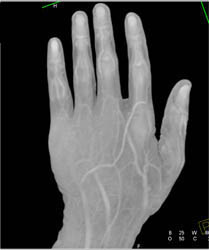

Soft Tissue Swelling